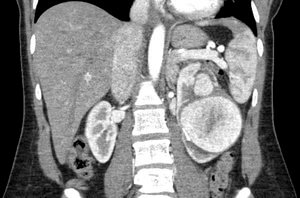

34 year old post-partum female who presented to her gynecologist with left-sided flank pain.

Comment: This post-partum patient developed a very large left renal artery aneurysm that was at significant risk for rupture. Given the size of the aneurysm and the branch of the renal artery supplying the aneurysm, we proceeded with embolization of the feeding vessel with an Amplatzer Vascular Plug. This has ultimately led to thrombosis of the aneurysm, as evidenced on subsequent follow-up imaging with ultrasound.